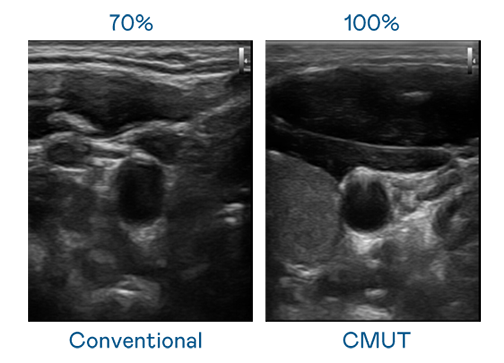

CMUT 技术是一种用电容式微机电元件来产生超音波讯号的技术。与传统 PZT 压电式技术相比,CMUT 频宽增加 30%,更宽频的超音波讯号让影像解析度大幅提升,是实现高影像品质医疗超音波扫描、促进精准医疗发展的关键技术。

大频宽带来超清晰影像

超音波影像的解析度高低,首先取决于探头能发出的讯号频宽。后宫露营第一季免费观看樱花动漫在线看 CMUT 可提供高清晰的超音波讯号,提供高频宽、高灵敏度、影像纹理细节更高的超音波影像,协助医护人员缩短影像判读时间及利用精准的医疗影像进行诊断。